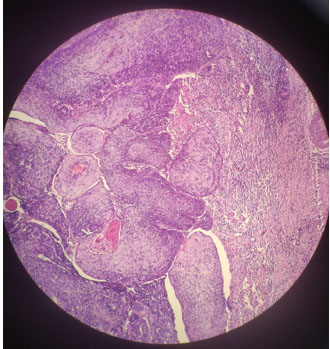

Furthermore, to accurately diagnose PPSCC, metastatic SCC of the parotid gland and high-grade MEC must be excluded [7]. High-grade MEC with a predominantly squamous component is very difficult to distinguish from SCC of the parotid gland with the aid of histopathologic examination, in contrast to SCC of the parotid gland, where low-grade and intermediate-grade MEC rarely cause diagnostic confusion. Also, MEC stain positive for intracellular mucin with PAS or mucicarmine stains which are absent in parotid SCC [8]. Almost all reported PPSCCs have been categorized as moderately highly differentiated and exhibit all the traditional histologic characteristics, as stated by Batsakis et al. for the creation of intracellular bridges, intracellular keratinization, keratin pearls, and a lack of mucin synthesis (Figure 2) [9].

Figure 2: Photomicrograph of the fine-needle aspiration cytology. The cells were heteromorphic, the mitosis was obvious, the ratio of nucleus to plasma was increased, and keratinized beads were formed.